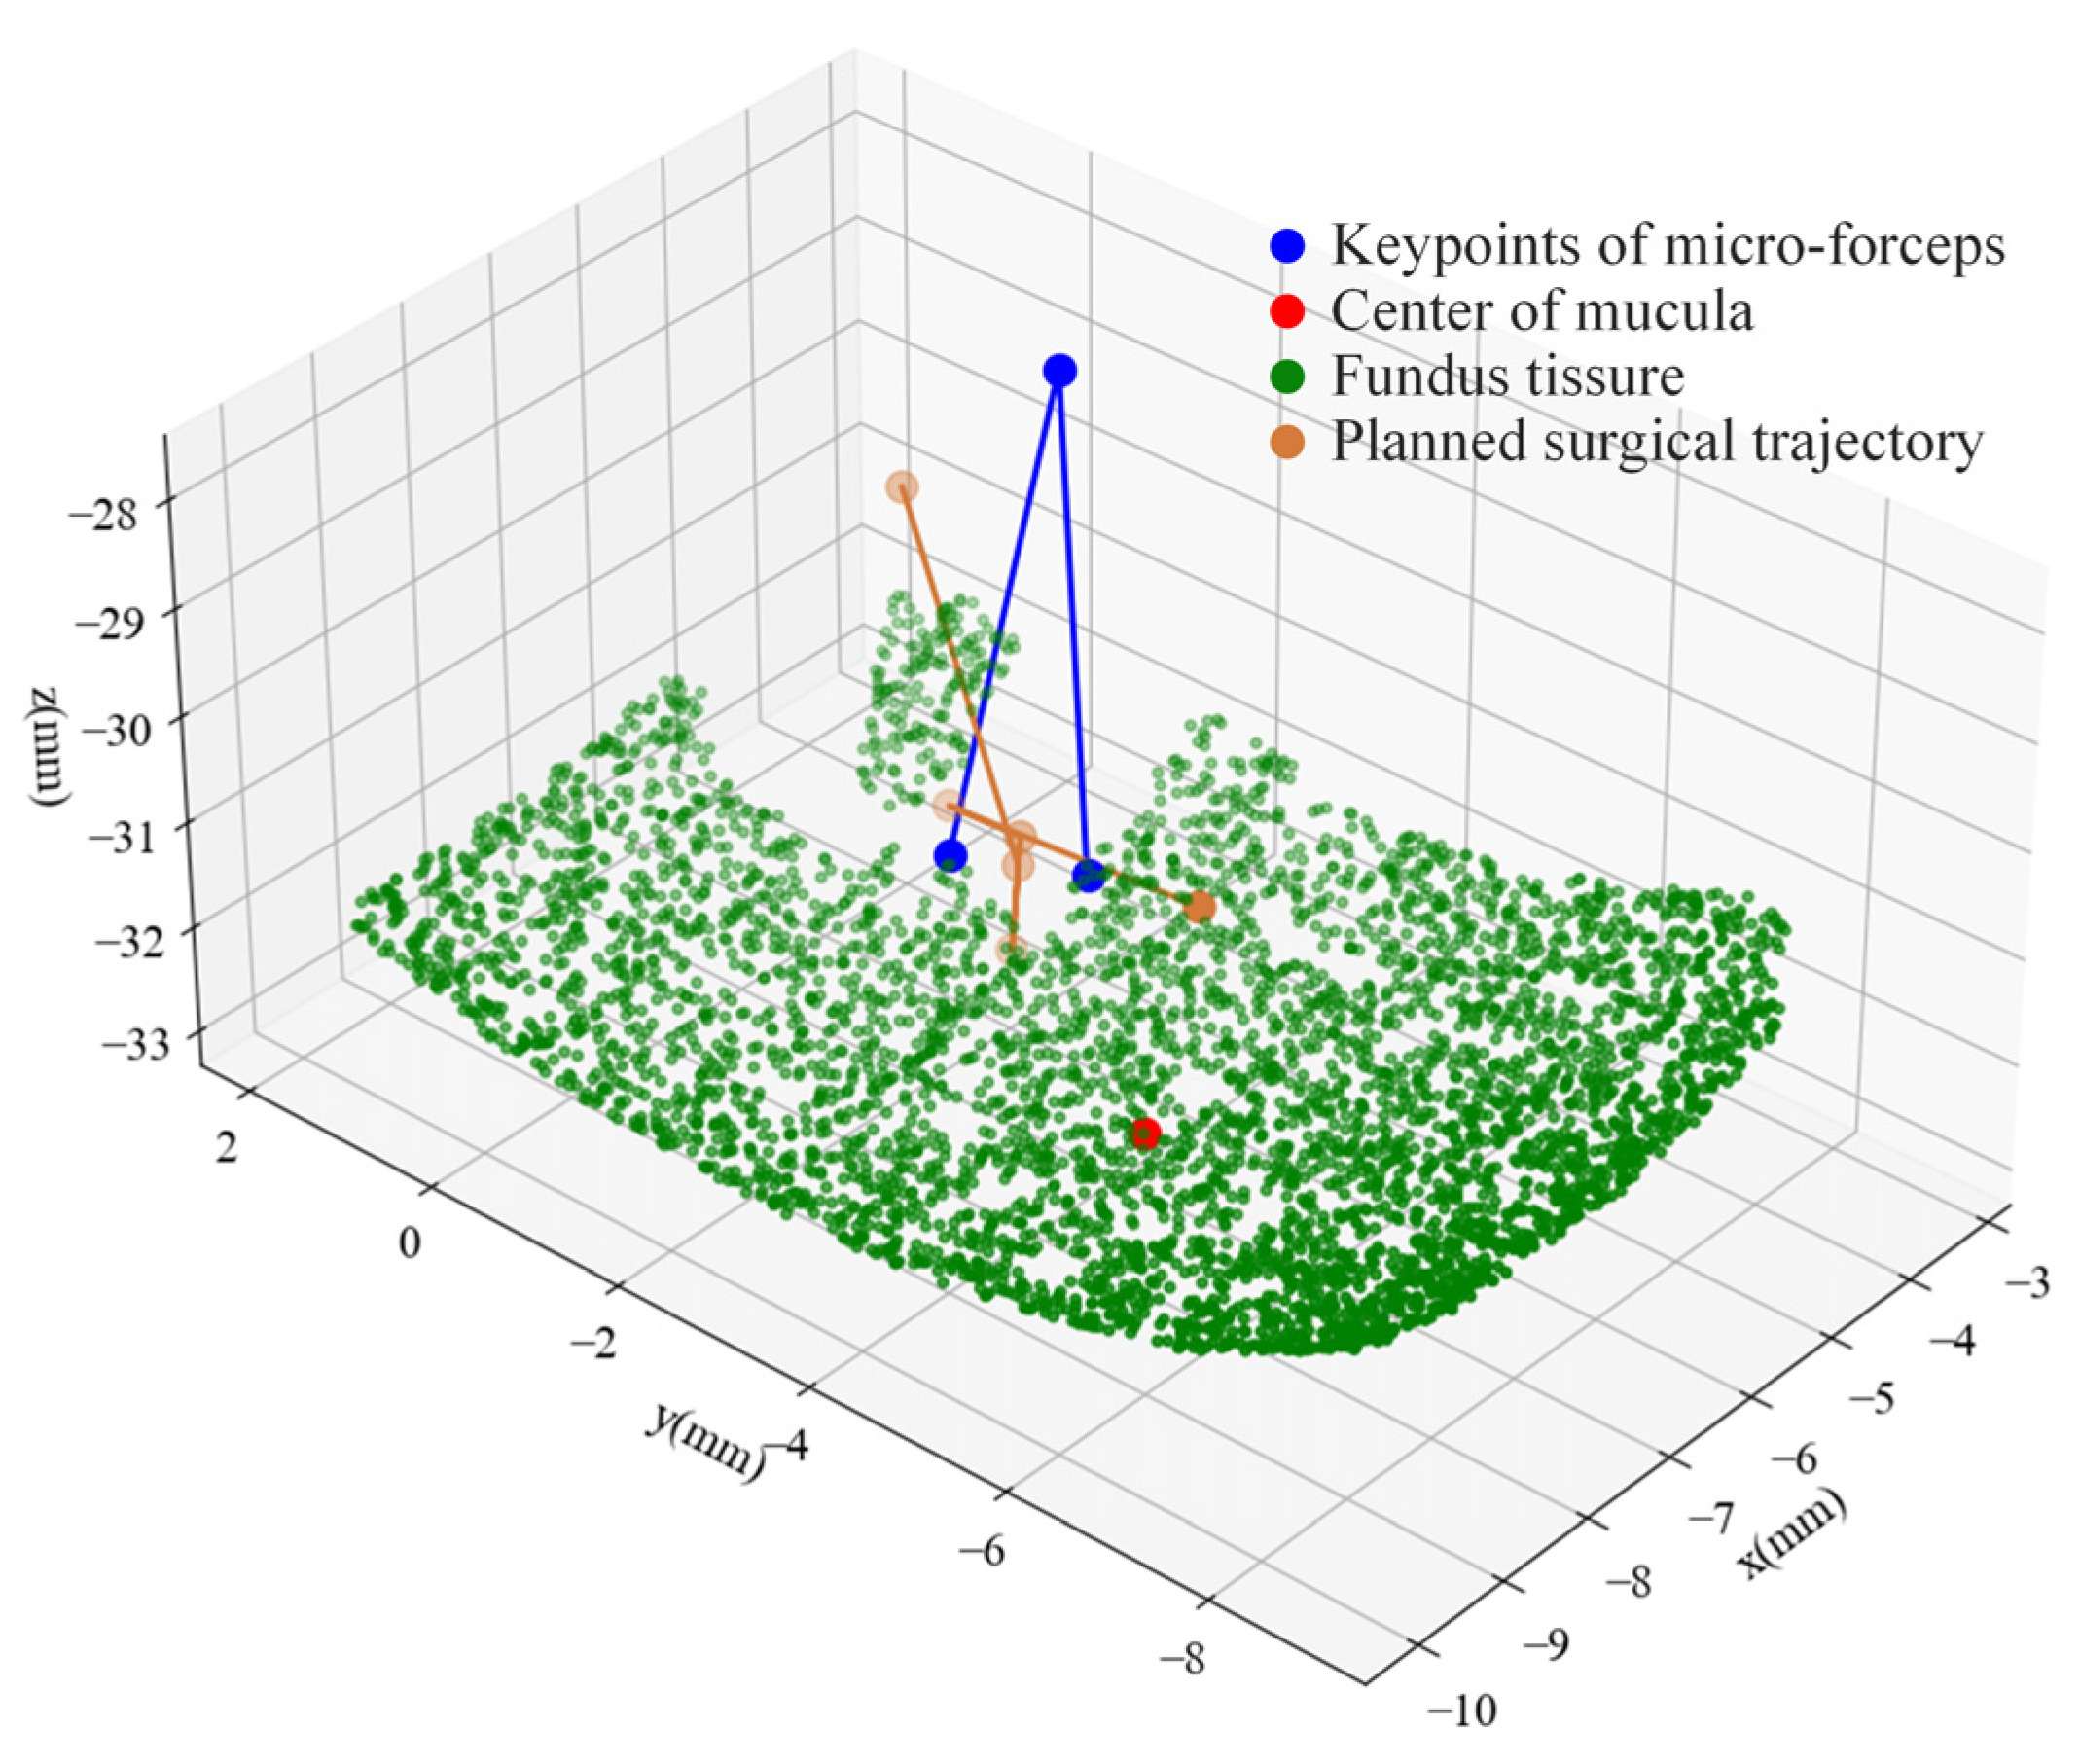

- A multivision task surgical scene perception method based on microscopic binocular vision combined with target detection, key point recognition, and sparse 3D reconstruction is proposed.

- An automatic surgical trajectory planning method for initiating breaks in the ILM during surgery is proposed.

2.4. Automatic Surgical Trajectory Planning Method